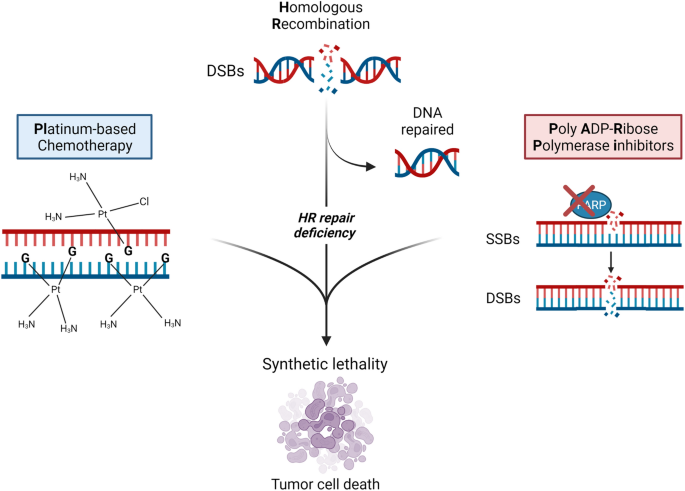

Platinum-based chemotherapy in metastatic prostate cancer: what possibilities?